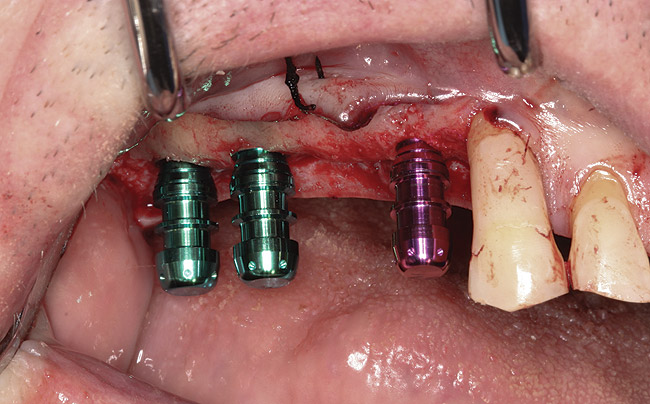

Drill depth gauge—A common complication of the crestal drill osteotomy is unintended perforation of the Schneiderian membrane. As a consequence, specific sleeves in different lengths were developed (Figure 8). These sleeves, which are placed on the drills, serve as gauge stoppers that prevent drill overextension. While the Cosci system uses only 3-mm-diameter drills, the newer systems include wider-diameter drills, which offer better visibility and control of the osteotomy and the integrity of the Schneiderian membrane. Figure 9 shows an implant insertion case using one of the newer systems to perform this crestal osteotomy technique. Osteotomy was performed with a non-cutting drill in 1-mm depth increments using depth gauge stoppers until the bone tissue is removed and the intact Schneiderian membrane is visible. The Schneiderian membrane is then elevated using bone-filling material, as described by Summers’ original technique (Figure 10). Following sufficient augmentation, the implants are inserted (Figure 11). Cone-beam computed tomography after 6 months reveals the bony mantle covering the inserted implants (Figure 12).

Fig 11. Dental implants are inserted through the crestal osteotomy preparation;

Figure 11